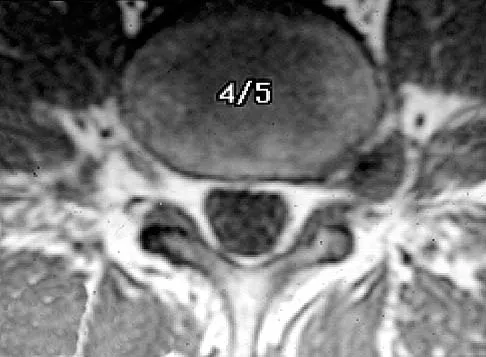

A 73-year-old woman reports a 4-month history of severe left-sided posterior buttock pain and left leg pain. The leg pain radiates into the left lateral thigh and posterior calf with cramping. Examination reveals mild difficulty with a single-leg toe raise on the left side and a diminished ankle reflex. There is also a significant straight leg raise test at 45 degrees which exacerbates symptoms. An MRI scan is shown in Figure 4. What is the most appropriate treatment at this time?

Detailed Explanation